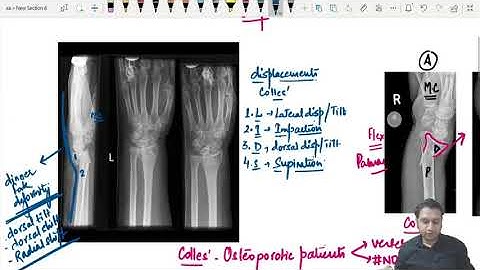

Colles Fracture Reduction and Plaster Technique